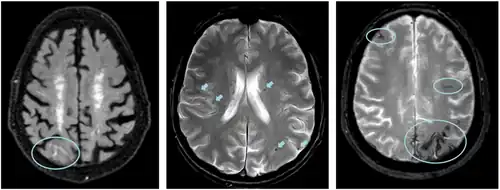

Mitte: ARIA-H (Mikroblutungen; T2*-Wichtung)

Rechts: ARIA-H (oberflächliche Hämosiderinablagerungen; T2*-Wichtung)

Amyloid-assoziierte Bildgebungsanomalien (ARIA) sind Unregelmäßigkeiten auf MRT-Bildern des Gehirns, die vor allem bei Einleitung oder Umstellung einer Therapie mit Anti-Amyloid-Antikörpern auftreten. Die Unterform ARIA-H repräsentiert kleine Blutaustritte, ARIA-E Flüssigkeitsansammlungen. Die Entstehung ist nicht vollständig verstanden, vermutlich kommt es durch einen Entzündungsprozess in den Blutgefäßen des Gehirns zu Schäden an den Gefäßwänden. Besonders häufig treten ARIA bei höheren Dosierungen und Menschen mit zwei Kopien der ApoE4-Variante oder Amyloid-Ablagerungen in den Blutgefäßen (zerebrale Amyloid-Angiopathie) auf. Meist handelt es sich um Zufallsbefunde, die keine Symptome verursachen, insbesondere ARIA-E kann durch die Schwellung jedoch zu Kopfschmerzen, Übelkeit und Verwirrungszuständen führen und einen Abbruch der Therapie erzwingen.[6]